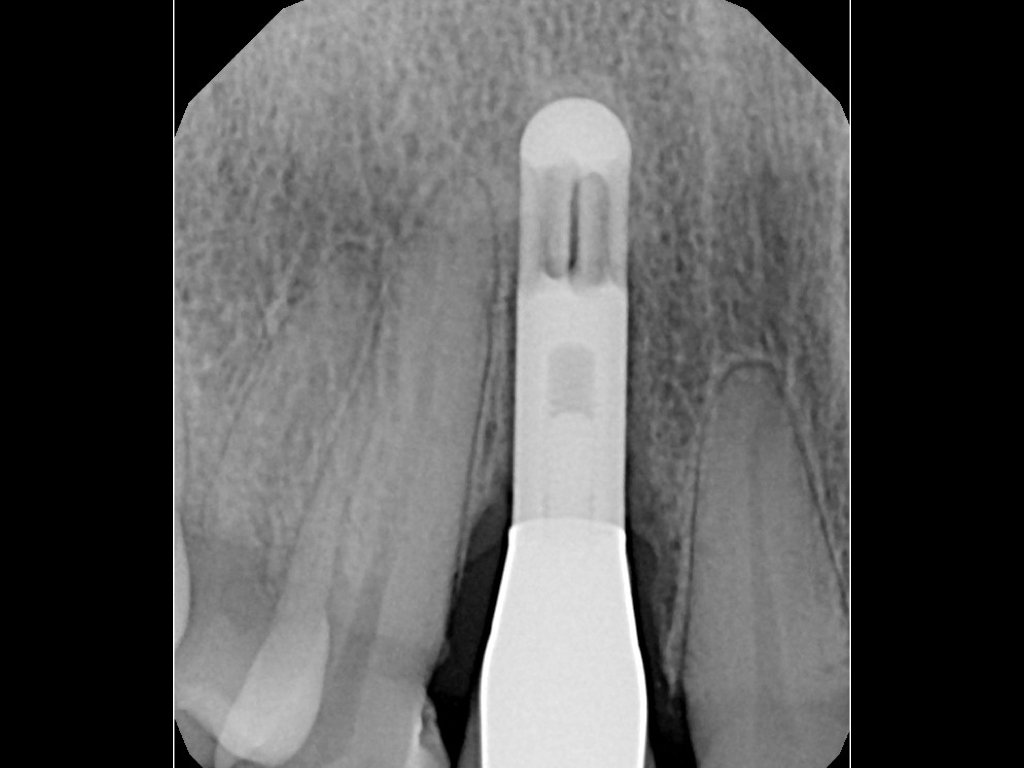

Clinical PPD is measured to the nearest millimeter by means of a graduated periodontal probe with a standardized tip diameter of approximately 0.4 mm to 0.5 mm. Several factors can influence the measurements made with periodontal probes, including: the thickness of the probe used5; the angulation and positioning of the probe depending on anatomic features, such as the contour of the tooth surface (Figure 1 through Figure 3)6; the graduation scale of the probe5; the pressure applied on the instrument during probing6; and the degree of inflammatory cell infiltration in the soft tissue and accompanying loss of collagen.7

Fig 1. Inaccurate probing angle wrongly indicates probing depth at 3 mm, which does not correspond to the radiographic finding shown in Fig 2.

Figure 1

Fig 3. Correct angulation of the probe demonstrates 6-mm probing depth.

Figure 3